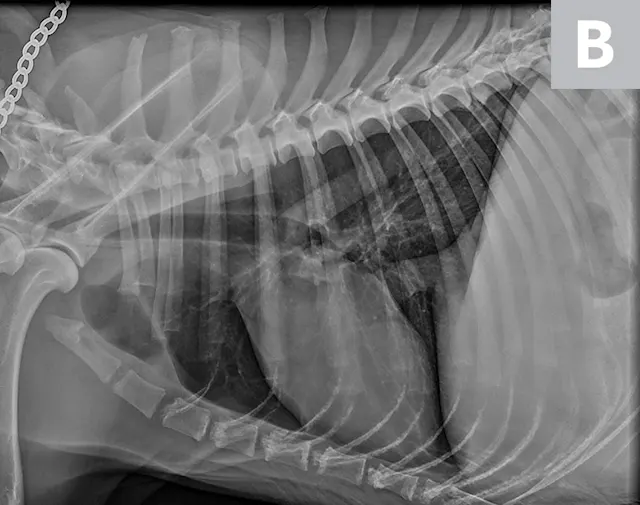

FIGURE 3A

Relative heart size difference on lateral thoracic radiographs of a normal basset hound (A) and a normal greyhound (B).

The cardiac silhouette can appear larger in small-breed dogs because the heart occupies a large amount of thoracic space; conversely, the cardiac silhouette can appear smaller in large-breed dogs (eg, greyhounds) due to the relatively larger size of the thorax (Figure 3).2